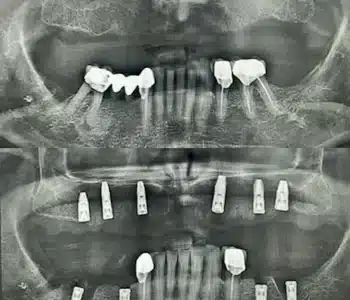

Dr. Seden Aksu is a specialist in modern implantology and surgical dentistry with extensive experience in the management of complex clinical cases. In her practice, she applies comprehensive surgical planning, minimally invasive techniques, and advanced regenerative technologies aimed at restoring both the function of the dentoalveolar system and the aesthetics of the smile. Dr. Aksu has significant experience in performing implant procedures, bone augmentation, and periodontal surgery, including the treatment of patients with severe bone loss. The primary goal of her work is to achieve stable, long-term outcomes in implant rehabilitation and the restoration of oral tissue health.